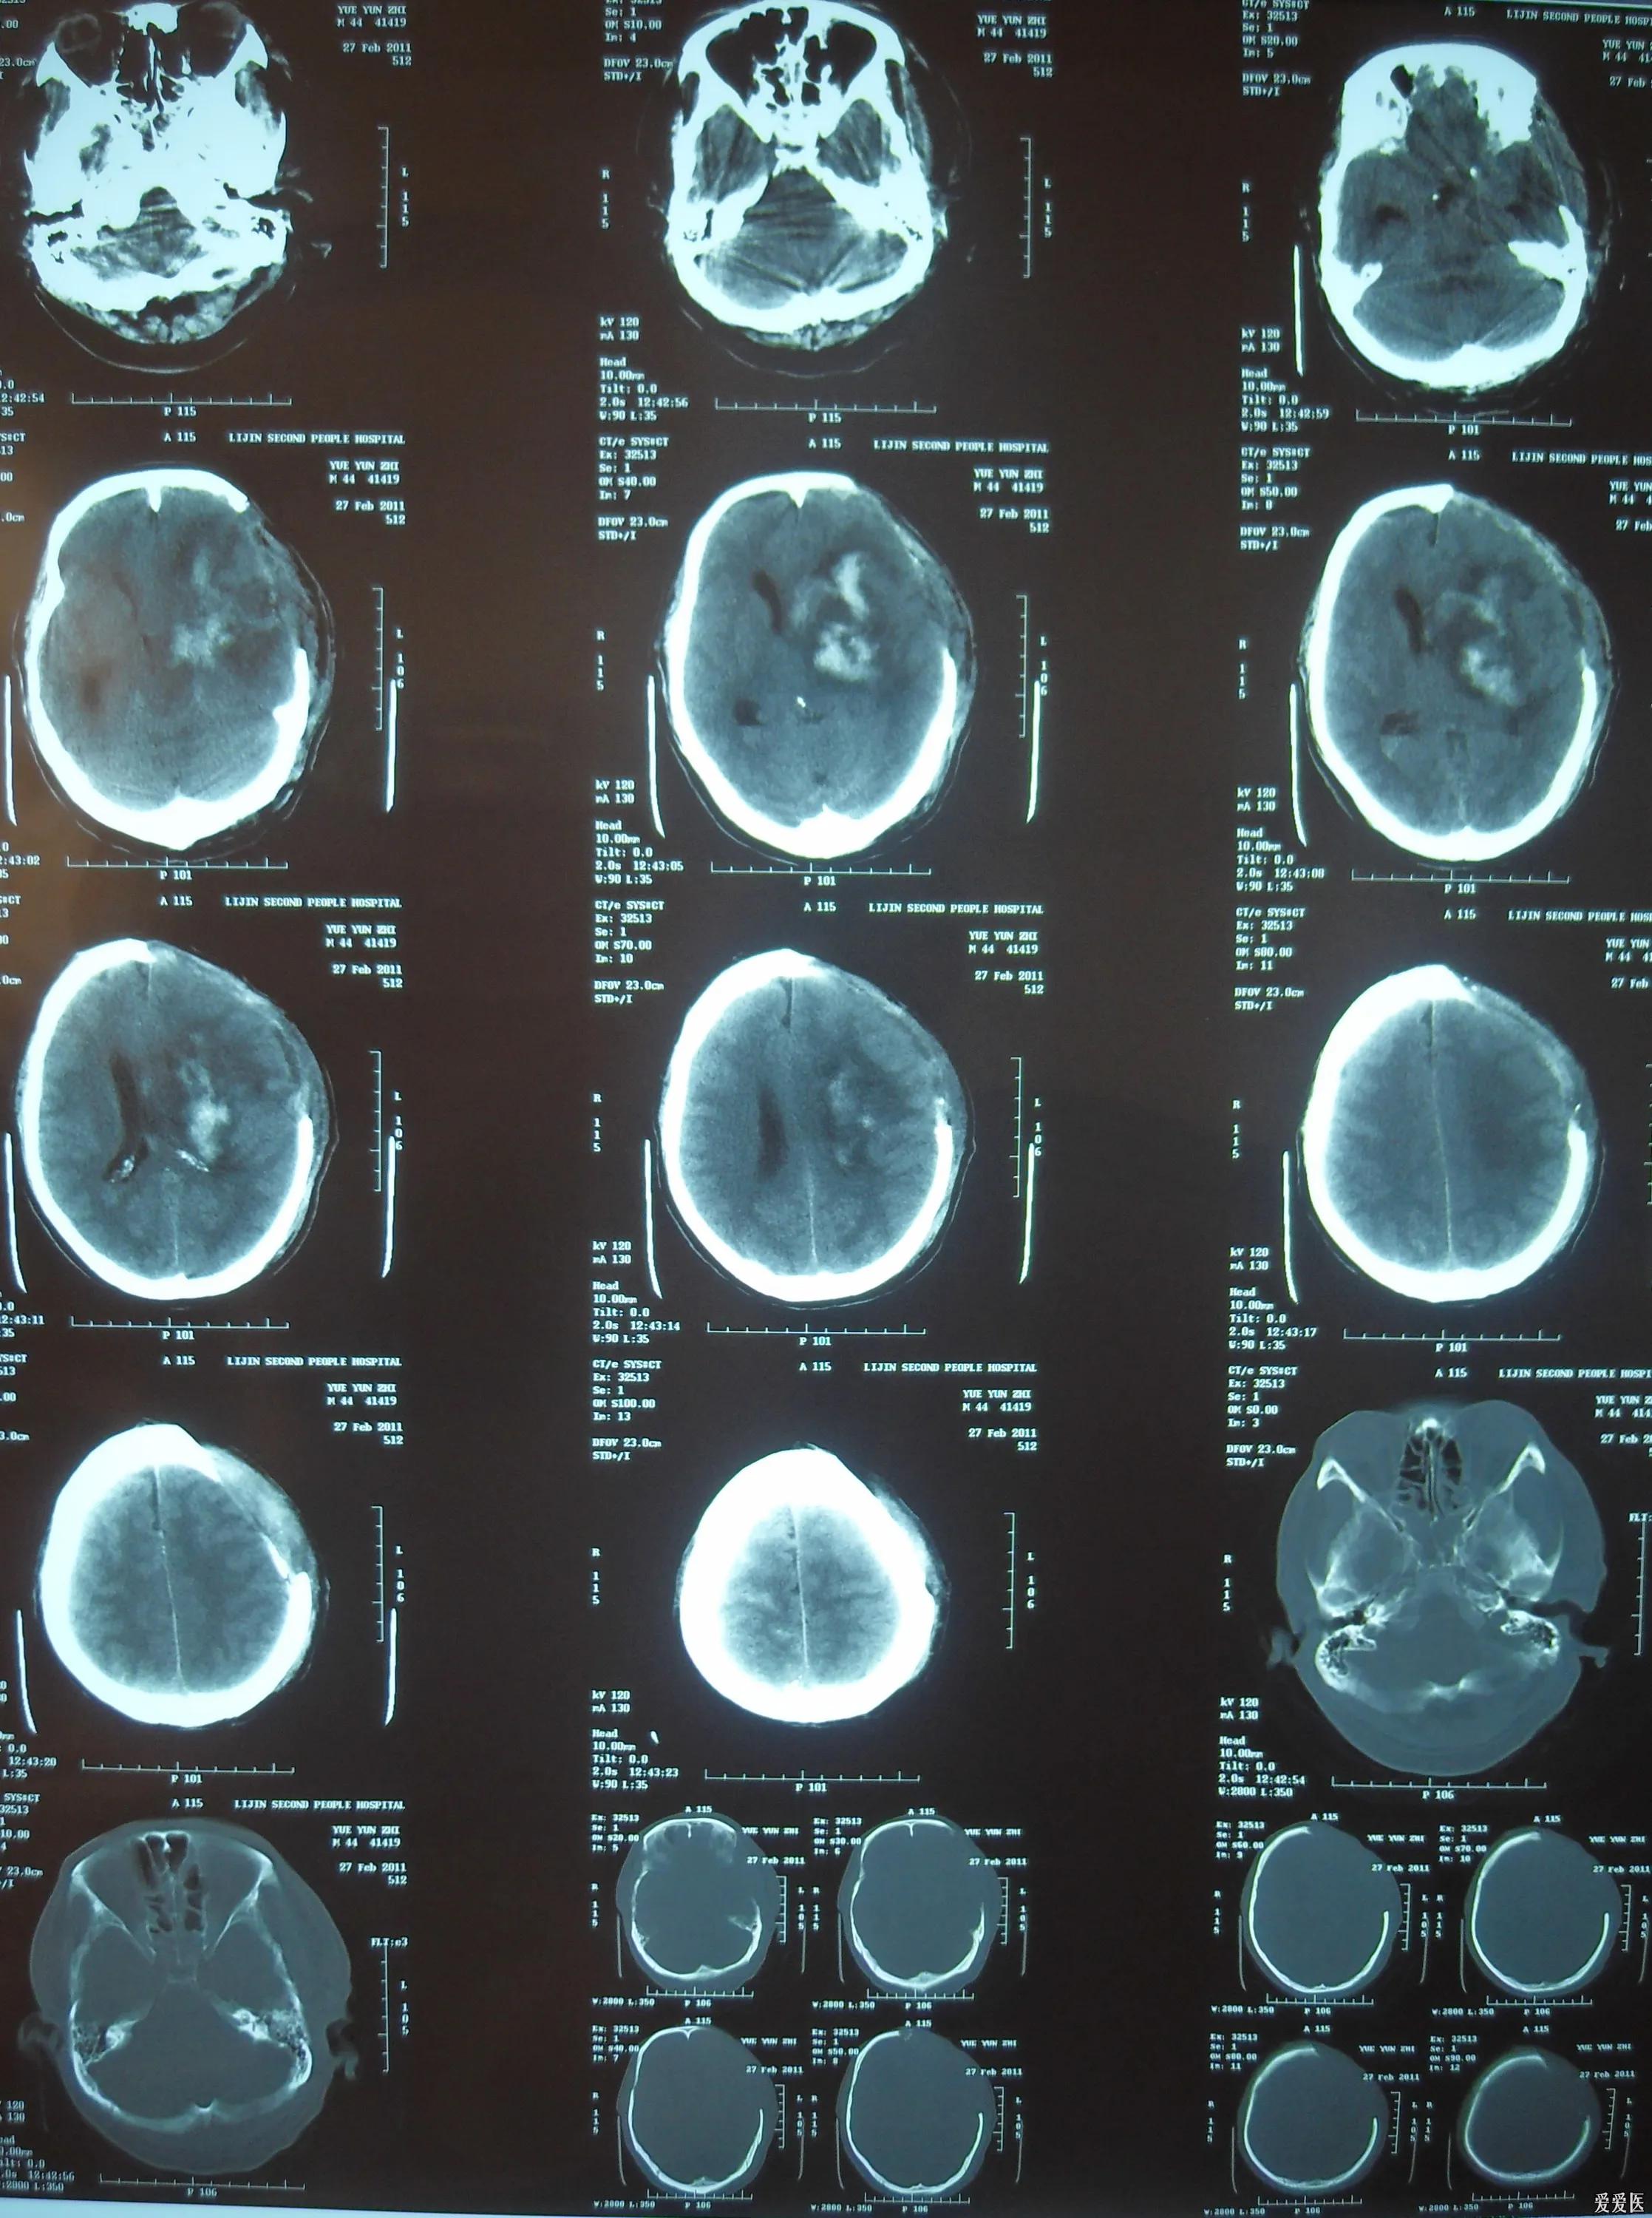

可是人生的大起大落来的实在太快了。真的让我猝不及防。2018年12月19日。也就是家里房子刚刚盖好还没来得及装修,我买车买房不到三个月,我父亲脑淤血住院。

父亲一病就是一年半,其中在医院8个月,在家将近一年。这一年半我请了假,中间上了两个月的班,挣了六万块钱。父亲一直到去世都没醒过来,喉咙的管子和鼻子的管子都是去世之后拔掉的。大家应该都知道,脑淤血的病人如果没醒过来,是很折磨人的。每天固定时间要喂流食,24小时每3个小时需要给他翻身,拍背。这个活我妈一个人做不过来。而我因为买了车,买了房,家里又盖了房,手里基本就没钱了。还好,之前家里有个超市,虽然我爸病了以后就没再开了,家里多少还是有点存款。2019年10月之前,我都靠自己的积蓄加上信用卡、网贷、找朋友拆借扛过来了。但是10月以后我就真的扛不动了。每个月我自己房贷加车贷一万多,加上乱七八糟的支出,一下子资金就周转不开了。